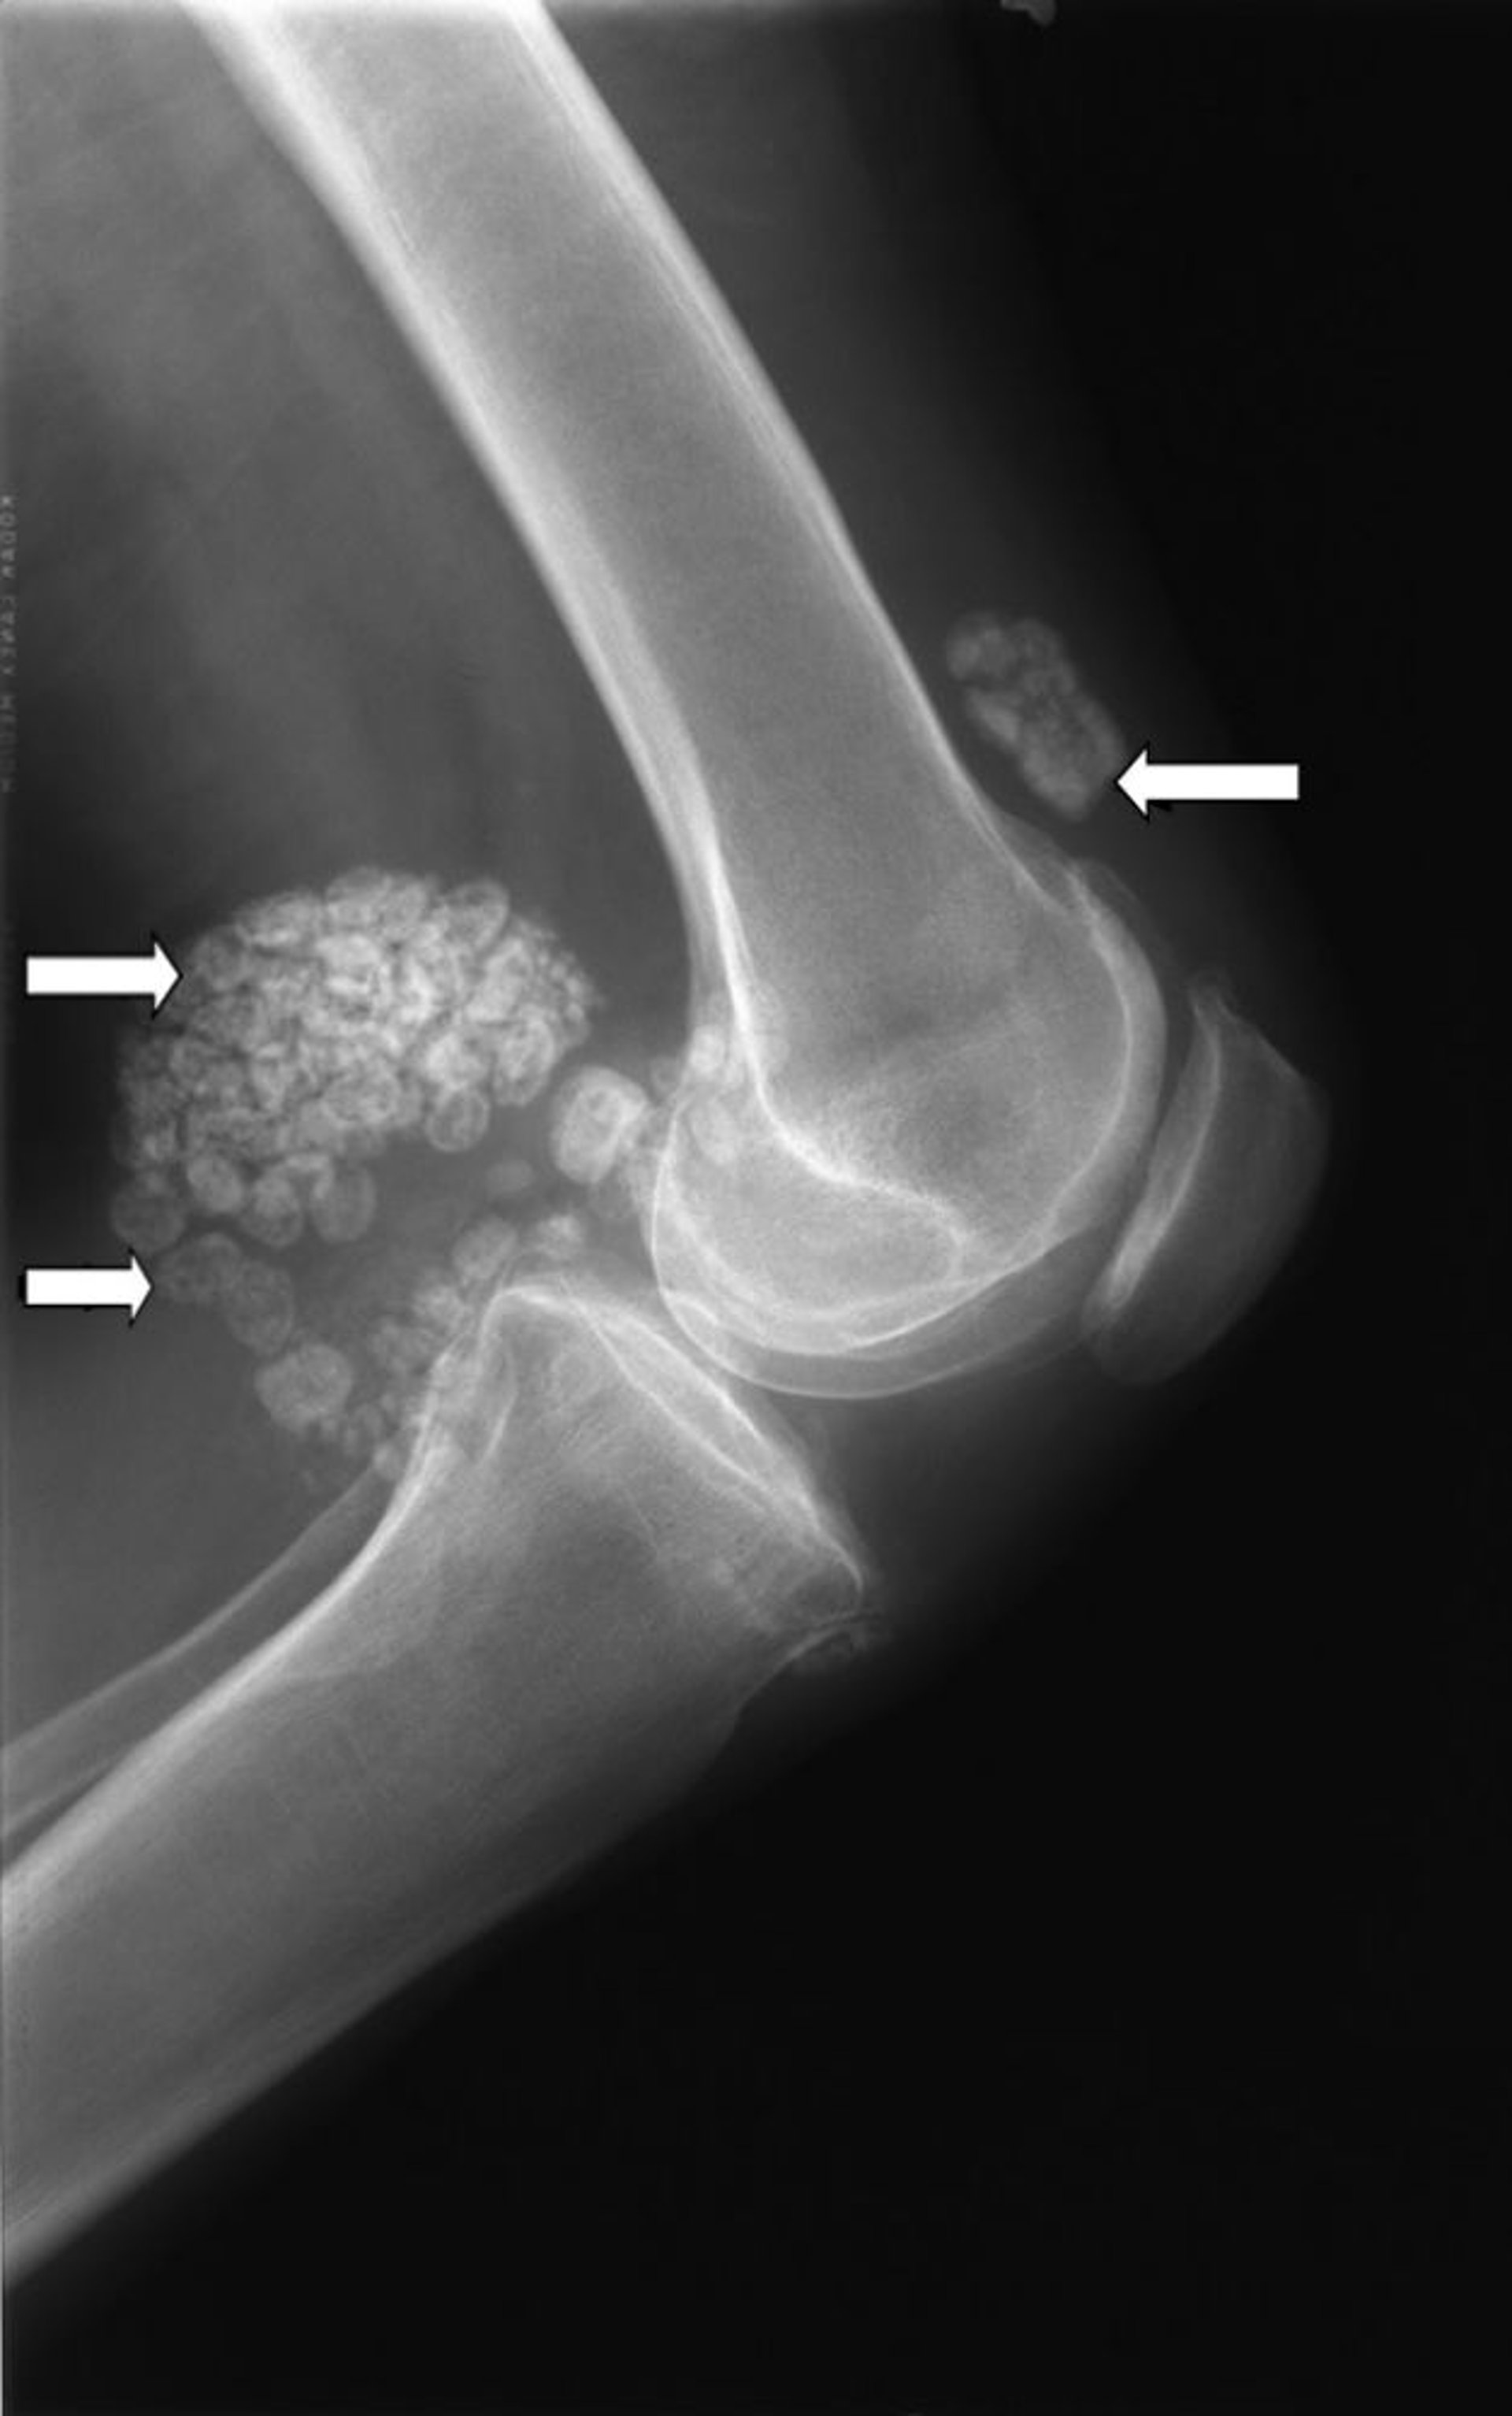

Синовиальный хондроматоз

На этой рентгенограмме колена показаны множественные узлы хрящевой ткани (стрелки), которые называются «синовиальный хондроматоз».

Изображение любезно предоставлено д-ром Майклом Дж. Джойсом (Michael J. Joyce) и д-ром Хаканом Иласланом (Hakan Ilaslan).